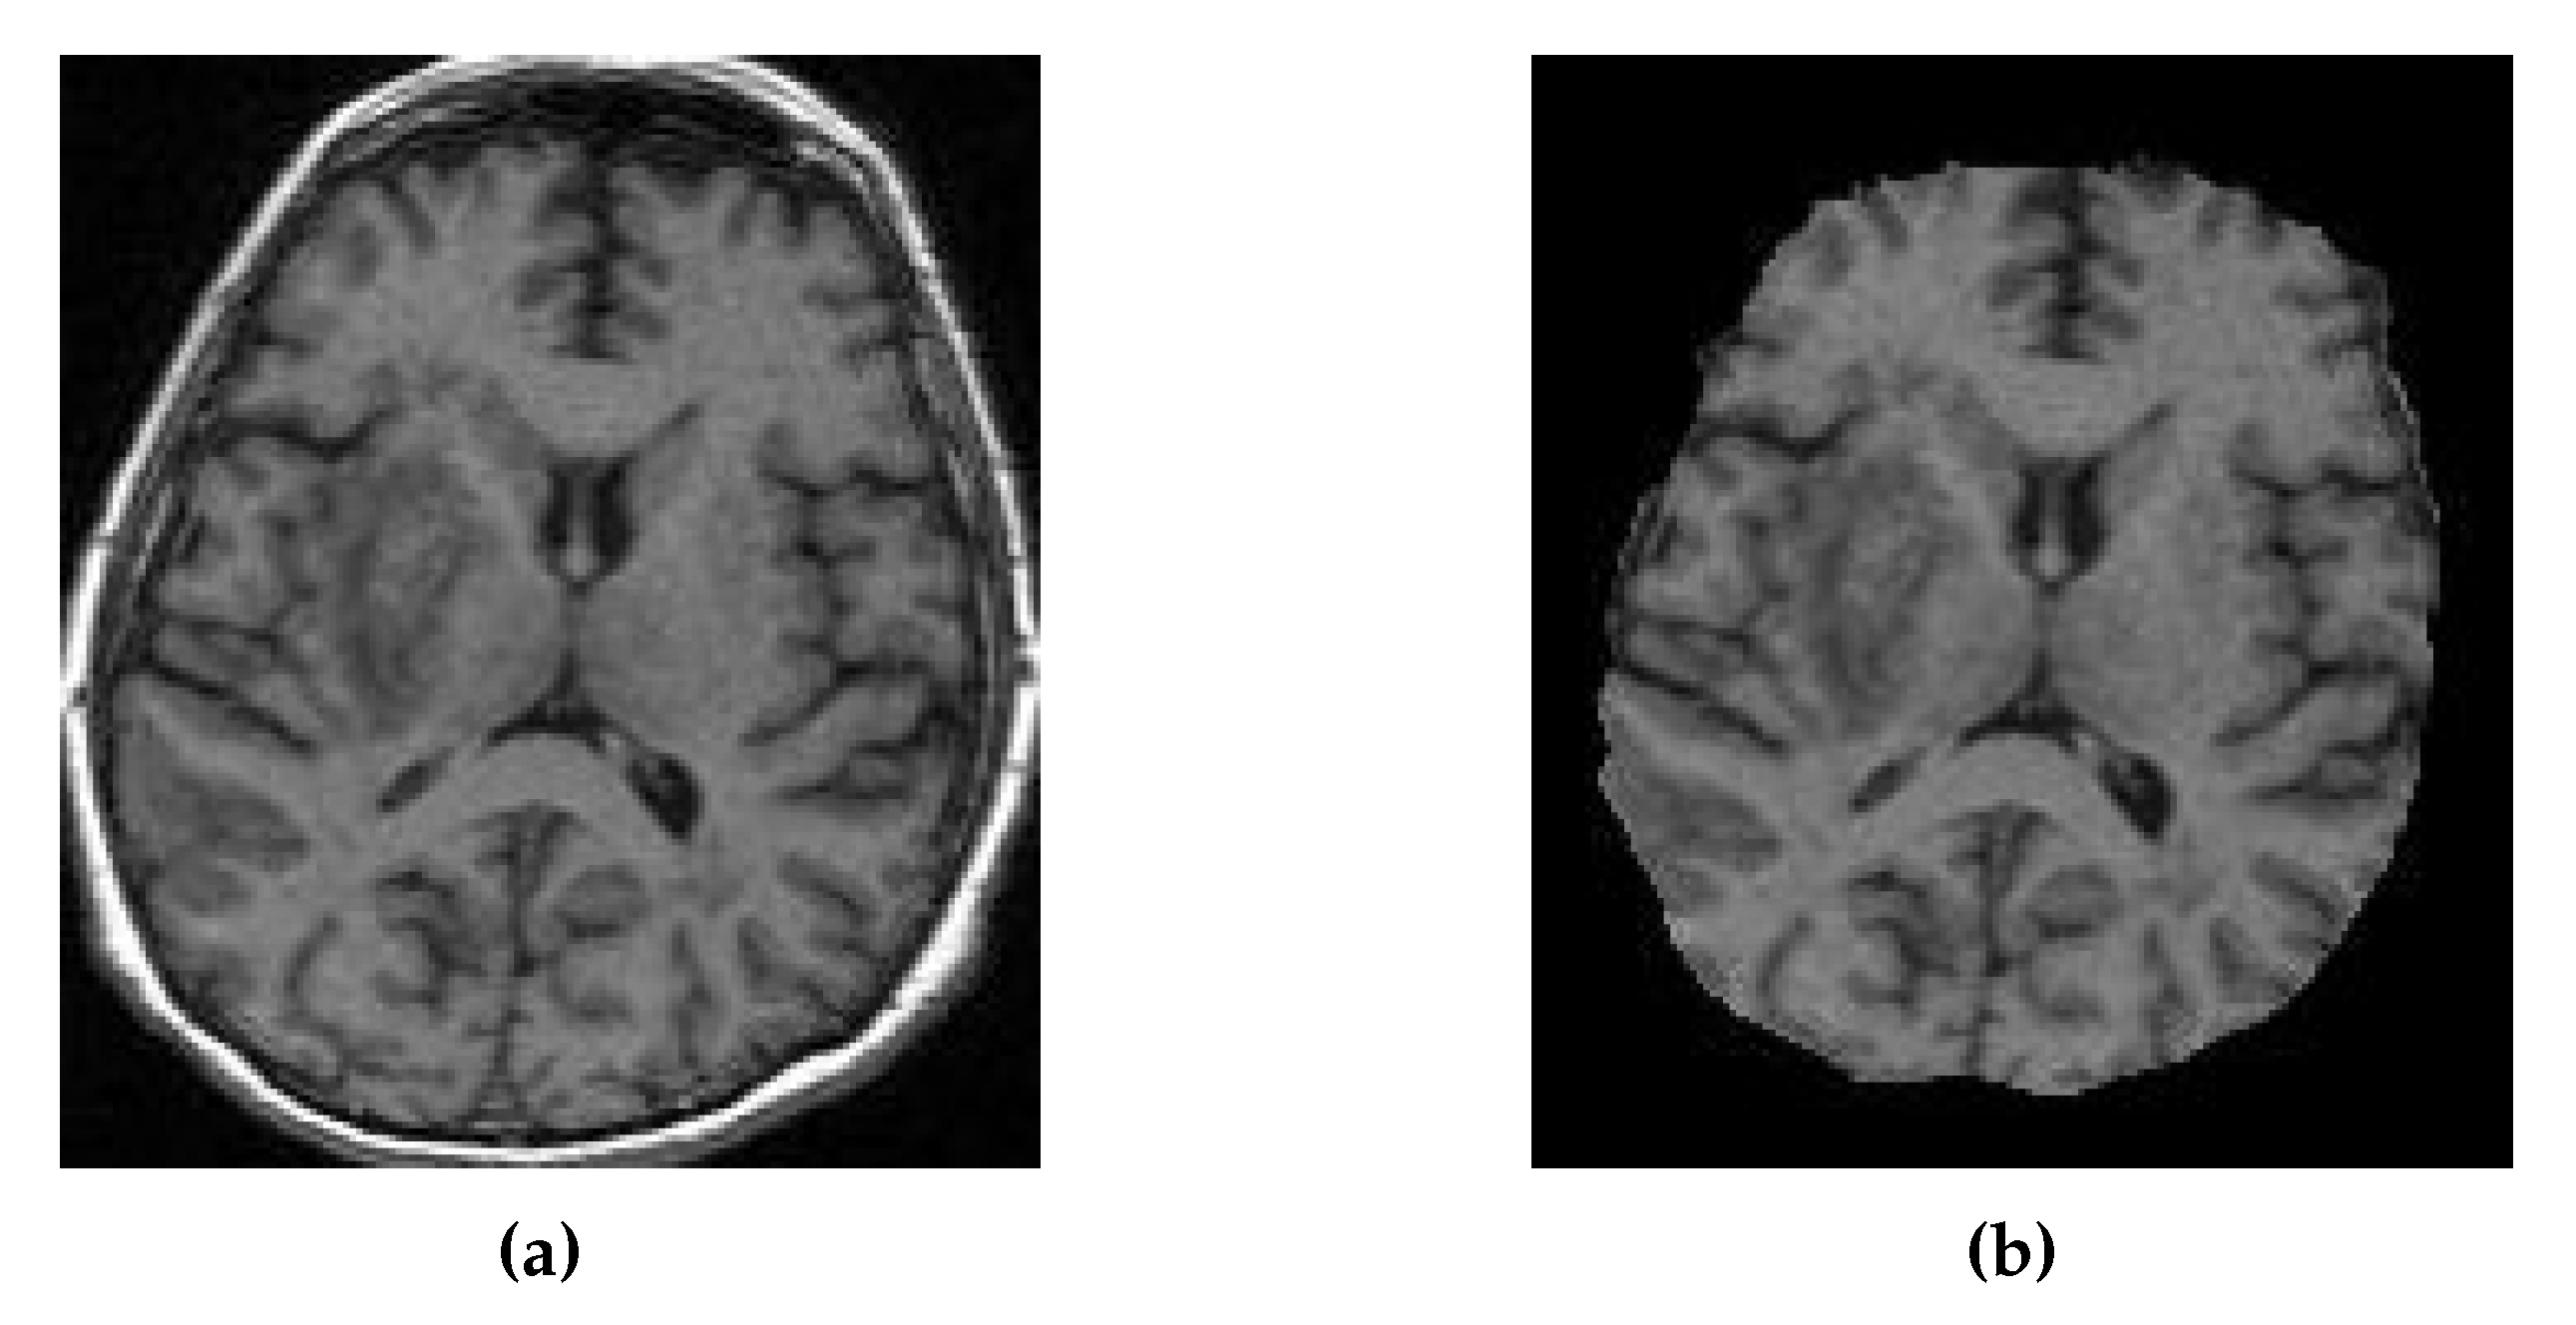

Figure 13 shows a slice of the synthetic MRI generated by a 3D UNet using an UpSampling layer and a Convolution layer instead of the Conv3DTranspose layer. The lesion for Patient A is clearly visible and appears similar in shape to the true MRI. The lesion in the Patient C is also discernible, albeit faint and lacking a clear outline. All three synthetic images show good contrast and likeness to the original image.

Figure 13. Axial slices of CT Scans (Left), True MRIs (Center), and Synthetic MRIs generated by UNet V2 (Right).

True CT True MRI Synthesised MRI

Patient A

Patient B

Patient C